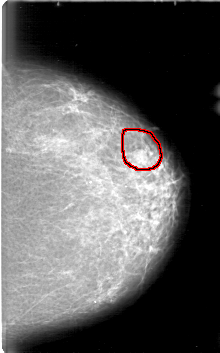

D_4089_1.LEFT_MLO

FILE: D_4089_1.LEFT_MLO.OVERLAY

TOTAL_ABNORMALITIES 1

ABNORMALITY 1

LESION_TYPE MASS SHAPE OVAL MARGINS OBSCURED

ASSESSMENT 0

SUBTLETY 3

PATHOLOGY BENIGN

TOTAL_OUTLINES 1

BOUNDARY